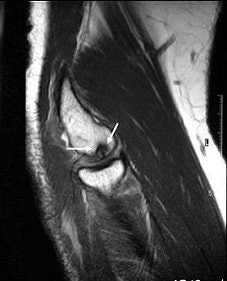

![]() |

| Sagittal MRI of JOCD on 1.5-tesla scanner. Protocol included FSE and T2-weighted imaging (TR/TE 3500/55). Image courtesy of Dr. Nancy Major, Duke University Medical Center, Durham, NC. |